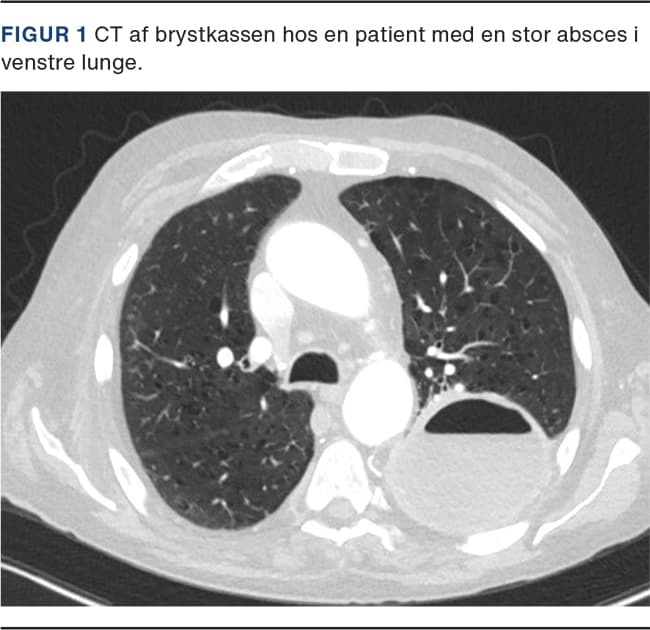

Konventionel røntgenoptagelse af thorax vil ofte være den førstvalgte billeddiagnostiske modalitet og kan vise en kavitet med luft-væske-spejl. CT af thorax med kontrast er hjørnestenen i påvisning af lungeabsces (Figur 1). Adskillelse af pleuraempyem med luft-væske-spejl og absces kan være vanskelig, men er afgørende for behandlingen, da empyemer ofte bør drænbehandles.

En lungeabsces er oftest lokaliseret til det posteriore segment i overlapperne eller apikalt i underlapperne. Størrelsen kan variere fra få cm til over 10 cm, men er oftest 4-8 cm [7].

Lungeabscesser adskiller sig fra pleuraempyemer ved at have samme udformning i alle projektioner, være omgivet af lungeparenkym og invadere kar og bronkiesystemet, modsat empyemer, som displacerer disse. Lungeabscesser vil have en tyk og irregulær væg. Hvis abscessen ligger i relation til thoraxvæggen, vil der mellem disse dannes en skarp vinkel. Pleuraempyemer har en tynd og uniform væg. Adskillelse af pleura viscerale og pleura parietale vil oftest kunne ses ved pleuraempyem [11, 12].